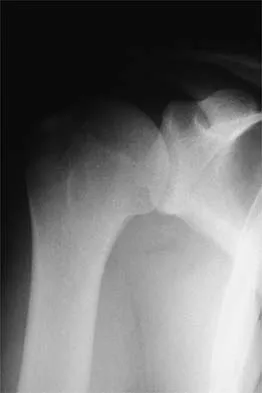

Figure 37 shows the radiograph of a 23-year-old football player who sustained a blow to the anterior aspect of his shoulder. Examination reveals pain and limited rotation. He is unable to flex the arm above the shoulder. Management should include which of the following studies?

Explanation